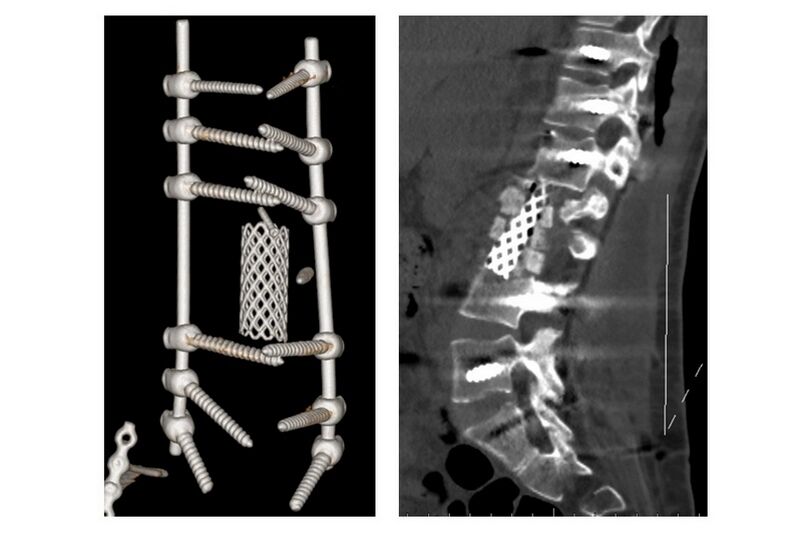

•07.04.23Мировые эксперты признали разработку курганских и томских ученых лучшим изобретением в медицине

•21.06.22Курганское изобретение вошло в десятку лучших медицинских изобретений России